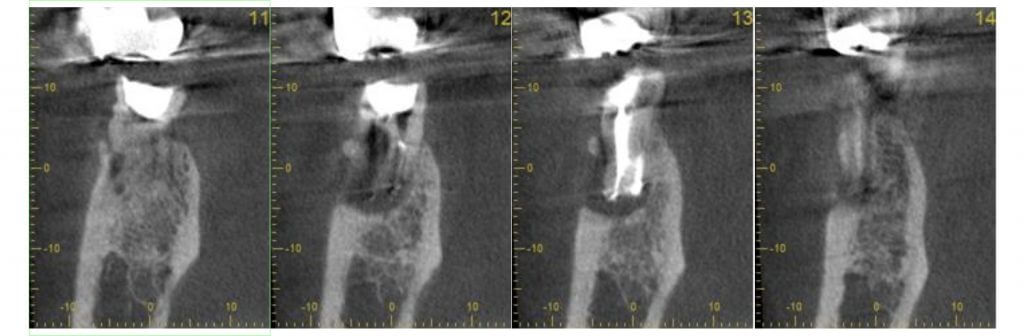

それが、最初にレントゲンを見た感想です。後日、歯科用CBCTを撮影してみるとやはり近心根の根分岐部あたりにパーフォレーションを疑わせる透過像が認められました。

術前、術中、術後ですがどうでしょう?

近心根と遠心根の透過像は少し縮小傾向が認められます。根分岐部の透過像もやや縮小傾向が認められ骨の再生を思わせる所見も見てとれます。

近心根の透過像が今だ完全に消失しないので数か月間経過観察後に歯根端切除もお話ししていますが

今のところすごくよく咬めるし痛くないと患者さんは喜んでくれています。